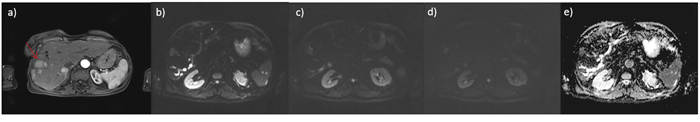

A total of 62 HCCs were evaluated (median 1.82 lesions; diameter between 12 and 20 mm). All tumors were histologically classified according to the major Edmondson-Steiner grade on final pathologic reports as follows: 14 with grade 1, 30 with grade 2, 18 with grade 3, and no one with grade 4. Figure 1, 2 and 3 report example of HCC of grade 1, 2 and 3 respectively.

Figure 3: HCC on V hepatic segment G3; in a. VIBE T1 weighted image, in b. DWI image at b value 50 s/mm2, in c. DWI image at b value 400 s/mm2, in d. DWI image at b value 800 s/mm2 and in e. ADC map.